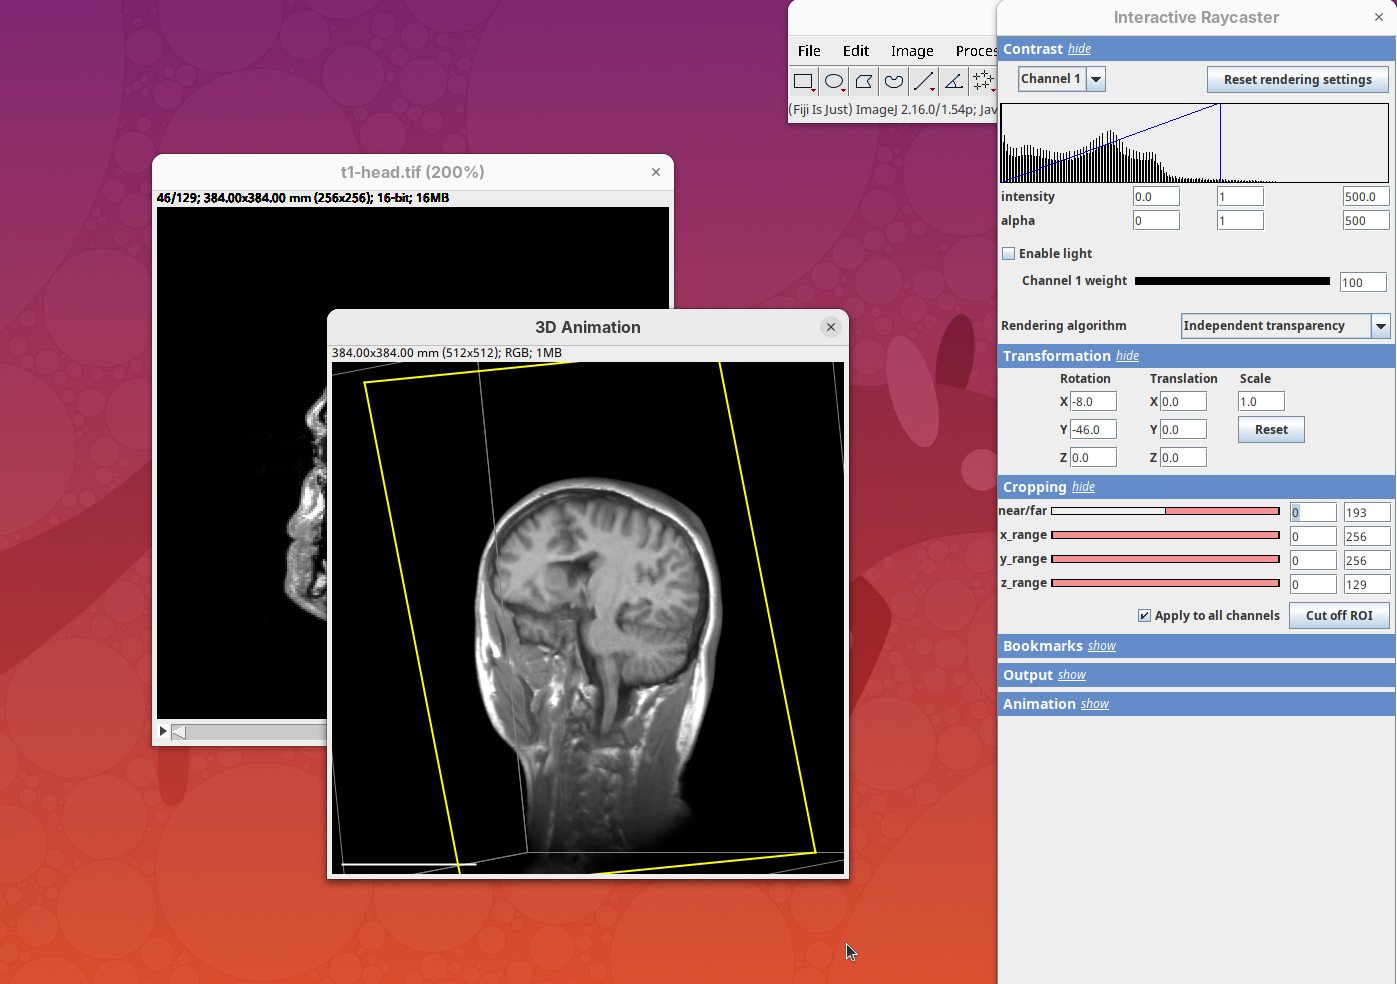

Plugins>3Dscript>Interactive Animation.

Two new windows will open: 3D Animation with the initial rendering of the data and Interactive Raycaster with all the fields to control the rendering parameters.

Contrast

The Contrast section shows a histogram of pixel intensities of the image for each channel, which we can choose using the dropdown menu. We can set the minimum, gamma, and maximum values for the intensity and alpha (transparency) properties of each pixel. The weight option controls the general opacity of the channel (0=invisible, 100=visible). There’s also more advanced options like lighting and rendering algorithm which we’ll simply use the default states as they are usually good for most use cases.

Adjusting the intensity and alpha values is the most impactful way to improve the 3D rendering. With the intensity setting we can define which pixel value in the image corresponds to total black (minimum) and which corresponds to total white. It’s the same as in the standard Brightness & Contrast tool. By default, 3Dscript will load these values from the original stack. In this case, it loaded min=3 and max=521.

Transformation

The transformation menu has controls for rotating, translating, and scaling the sample. We can either add values or manually interact with the 3D Animation window to reorient the sample. Let’s try the latter.

Cropping

Another useful 3Dscript option is the ability to crop the bounding box to show the inside of the sample. We can do it in the XYZ directions or in the near/far axis, defined from the user point of view.